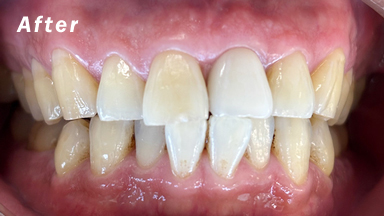

症例のafter画像

治療内容 インプラント

治療期間 3ヵ月

性別/年代 男性/40代

治療費 350,000円(税別)

治療のデメリット 保険が効かないため自費診療になり、外科手術が必要。又、治療期間が下顎で3ヶ月上顎で4〜5ヶ月の治療期間を要します。

インプラント術前、術後のレントゲンと口腔内写真です。術後18年の症例です。状態は良好です。